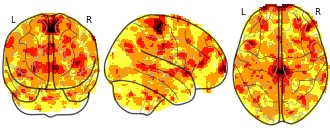

"name": "Multi_VBMgreater_fMRIenhanced",

"description": "Multi-modal analysis in BPD. Brain regions exhibiting greater gray matter and enhanced activation during emotion processing in BPD compared to healthy controls. Note: Results were thresholded at p<.0025. Note2: Results were updated (see Erratum for this publication).",